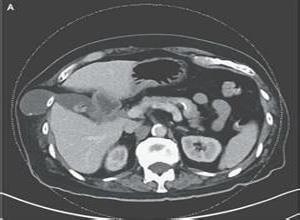

简介经膈肌肋间疝(transdiaphragmatic intercostal hernia)是腹内脏器经膈肌由胸壁“薄弱区”膨出而形成的疝,Manrer和Blades(1946) 首次报道本病,准确、详细的描述了4例病人, Croce和Mehta(1979)以“肋间胸膜腹膜疝”的名称报道该病。Cole等(1986)命名该病为经膈肌肋间疝。